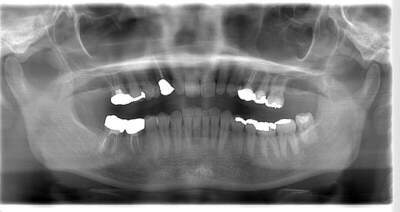

初診時のパノラマ

説明:

初診時のパノラマです。左下の一番奥の歯が虫歯になっているのがわかります。

初診時のパノラマレントゲン

初診時のパノラマレントゲンです。右上の歯が虫歯によって大きく欠けているのがわかります。